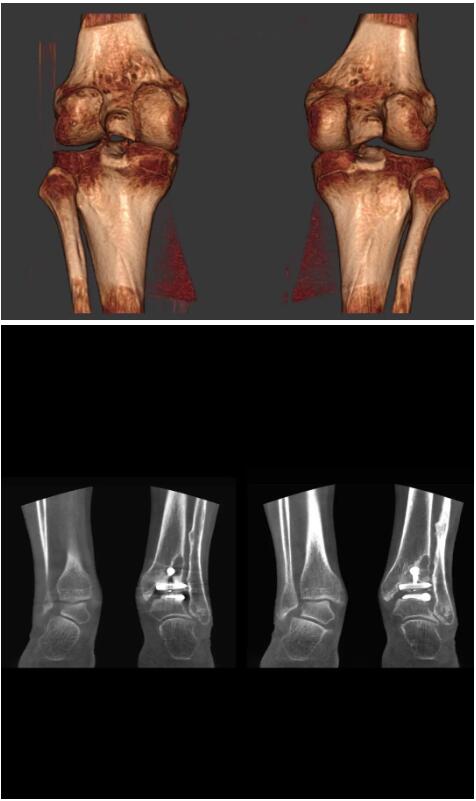

另外一款被稱為世界上最小的CT,它的重量?jī)H300磅,不僅能夠掃查足部,還可以檢查膝蓋和上肢等。

與上面介紹的CT一樣,它同樣具有輻射低、占地空間小(23*36)的特點(diǎn),隨開(kāi)隨用(支持直接接入墻上的插座)。

這款CT使用非常方便,通過(guò)上下移動(dòng)保持與患者的手臂或者雙腿齊平,掃描快速,僅需要30秒左右就可以完成掃查。

以上介紹的CT均來(lái)自國(guó)外同一家公司,這些CT均配置了可視化軟件,可以進(jìn)行切片、3D重建以及大型CT附帶的所有典型的操作功能。

以下是這些“特立獨(dú)行”的CT所拍出來(lái)的圖像: